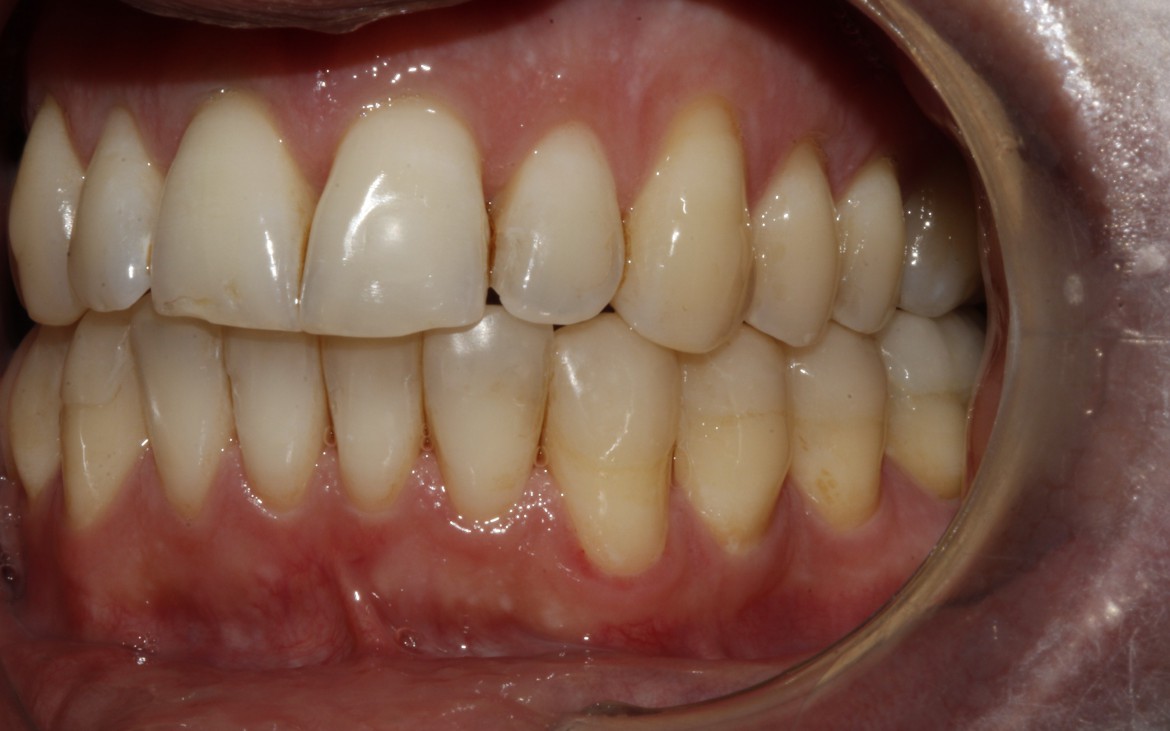

2- Oclusão classe ii de angle.

Ausência de guia anterior e guia lateral exercida em demasia pelos 1° pré-molares.

(vista lateral esquerda.)

24- Vista lateral direita – caninos e molares corrigidos na relação oclusal classe I de angle.

Overjet ou discrepância antero posterior, guia de lateralidade e guia anterior reestabelecidos.

25- Vista lateral esquerda: Caninos e molares na relação oclusal classe I de Angle. Guia de lateralidade e guia anterior reestabelecidos.